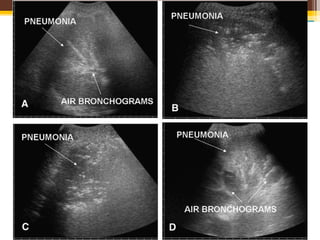

• 肺炎患者のCT

• これはどう見えるか?

Chest 2008;134:117-125

Posterolateral alveolar/ Pleural syndrome(PLAPS)

• AC; 肺胞内に水分貯留があり,

実質状に見える LLがAlveolar consolidation

深部はIrregular borderとなる(黒矢印). Air bronchogramはHyperechoicとなる.